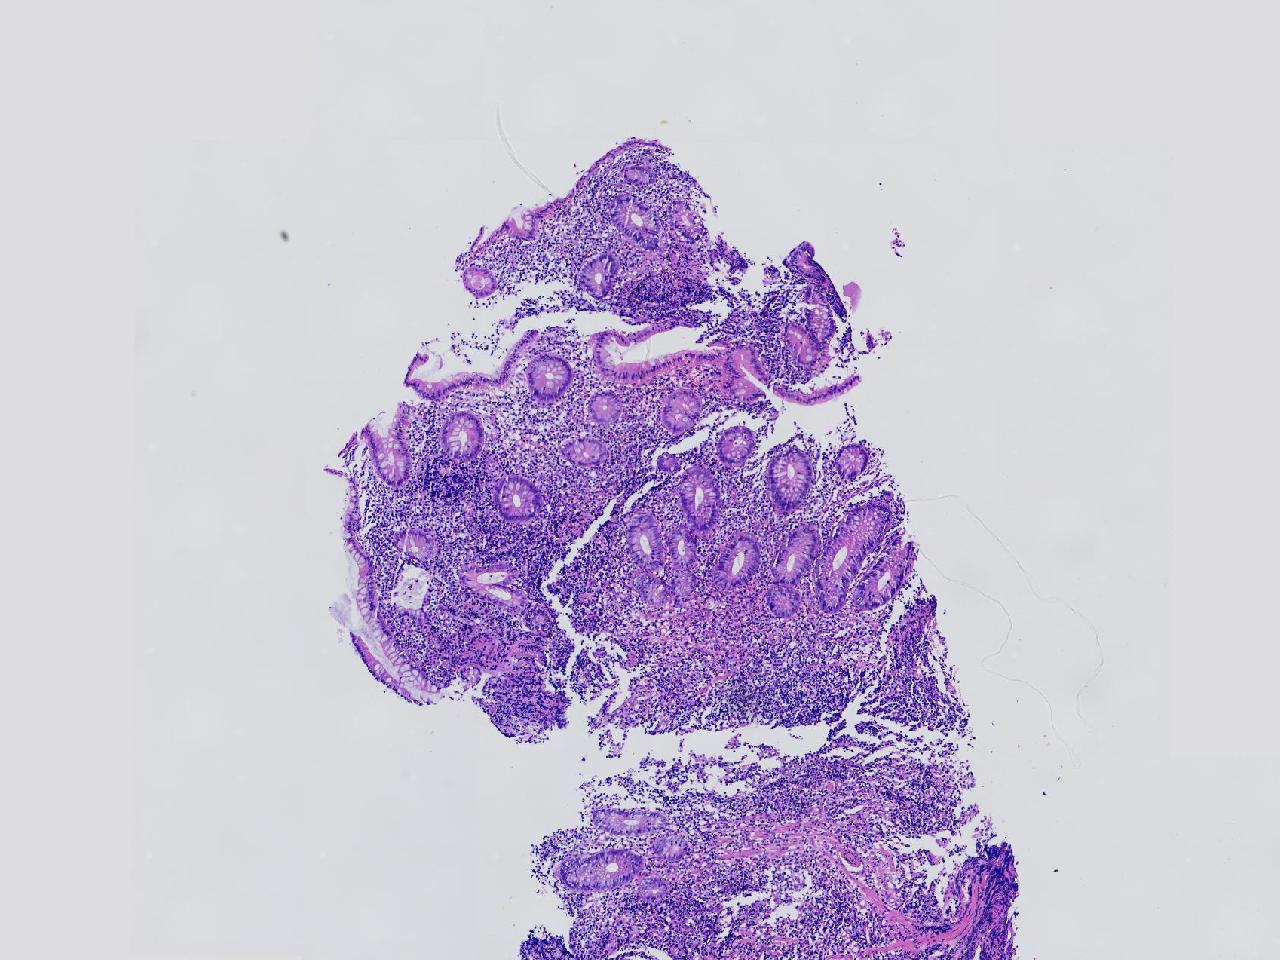

男,62岁,回盲部附近见多发片状溃疡,底覆薄白苔,周围粘膜充血水肿,活检2块,质软,弹性可。

回盲部活检

灰白色不整形软组织2块,直径均0.2厘米。

图1

考虑:溃疡性结肠炎?

炎症性肠病要考虑,具体的类型不太好确定,需要结合临床。

上级医院会诊,不除外炎症性肠病,结合临床。